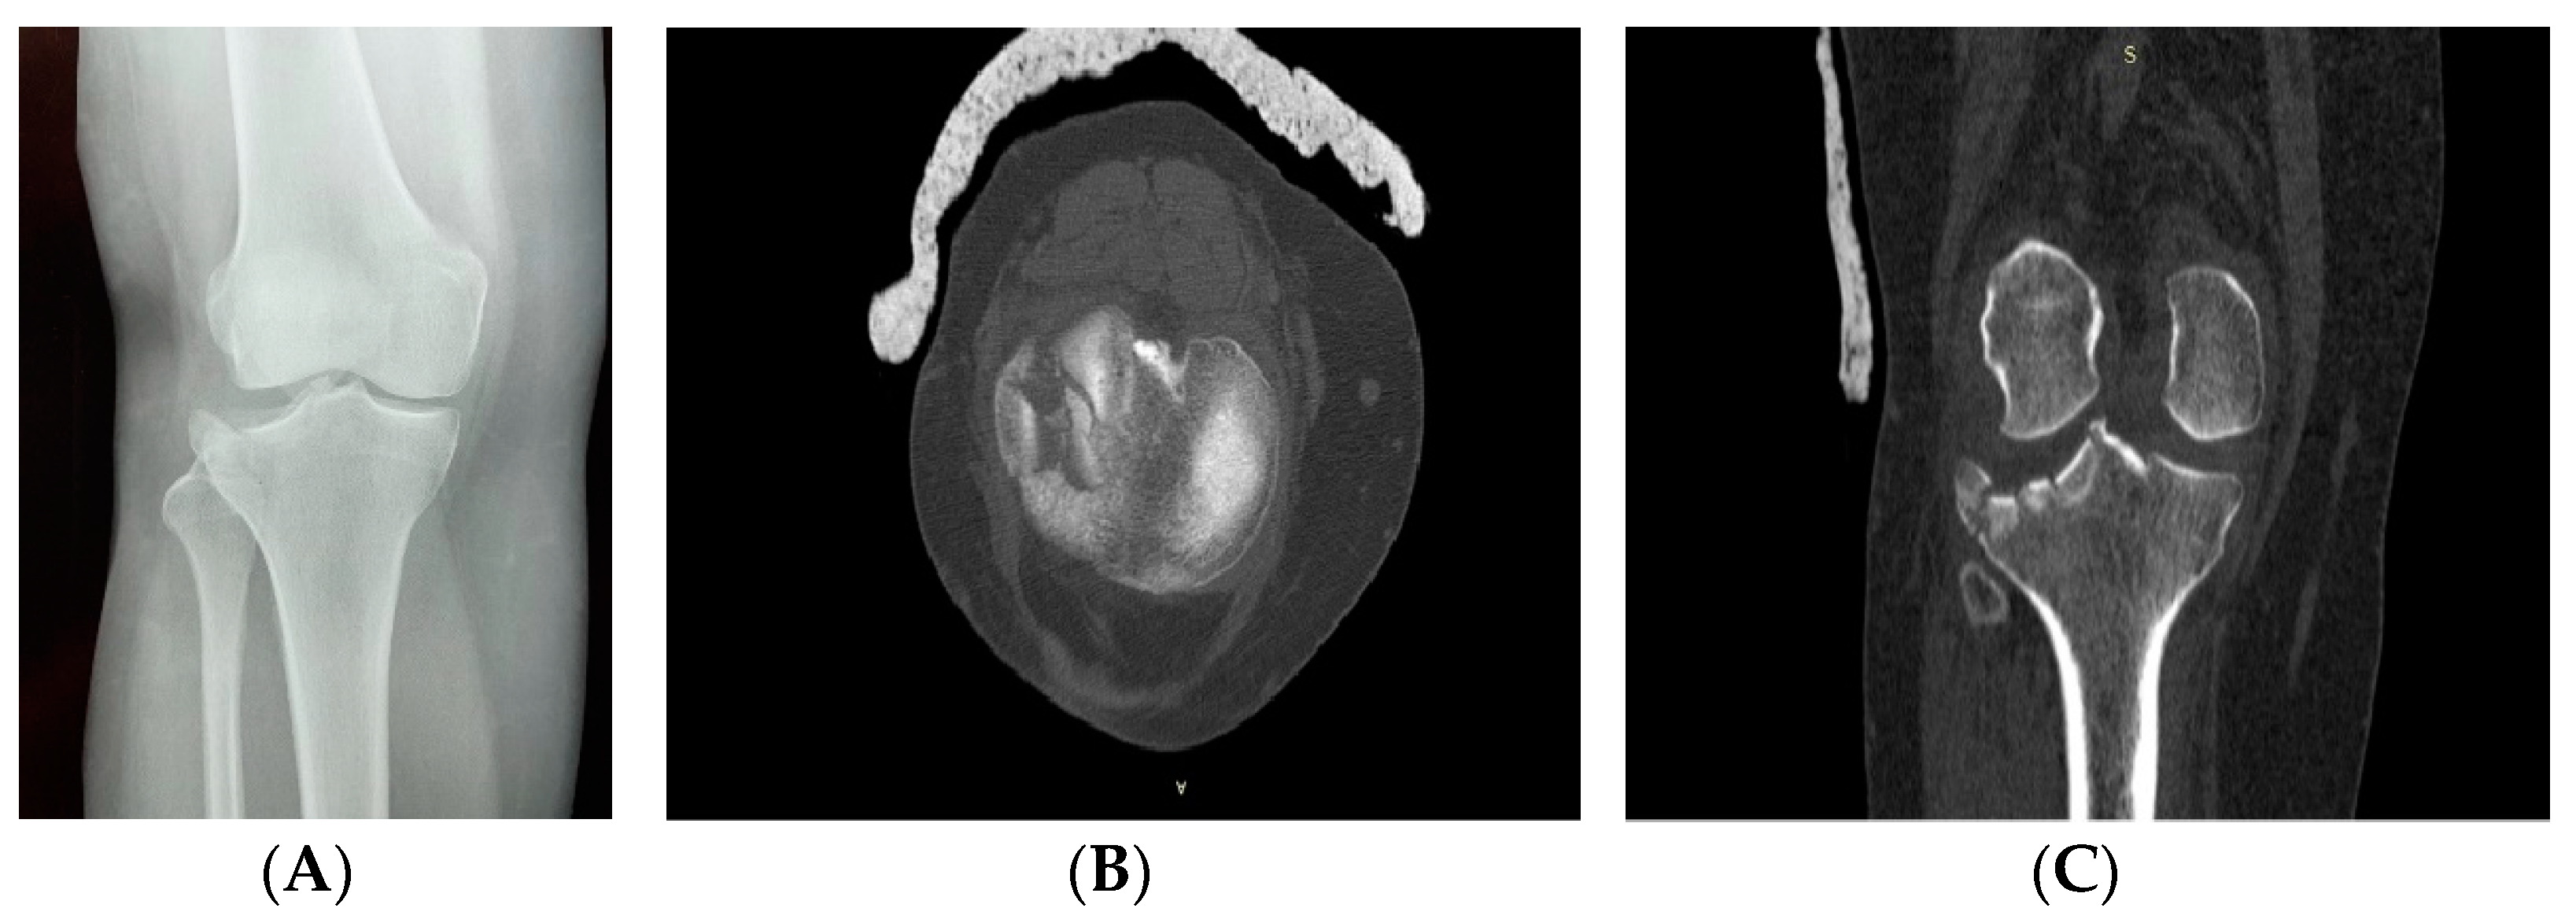

2. Clinical Case Presentation